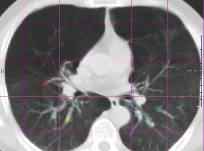

All results are available in Table 5. By combining features from both the registration and modality-independent intensity category, improvements were obtained in all evaluation measures.

The result of the regression with combined features is detailed in Fig. 6(a), which shows the real error (solid blue line) against the predicted error, sorted from small to large. In Fig. 6(b) we grouped the real errors in the three categories, each category showing a box-plot of the predicted errors. Intuitively, a smaller overlap between the boxes represents a better regression.

Refer to caption

Figure 6: Real (y𝑦y) vs predicted registration error (y^^𝑦\hat{y}) for Combined features in the SPREAD database. (a) The real error (solid blue line y𝑦y) against the predicted error (y^^𝑦\hat{y}), sorted from small to large. In (b) we grouped the real errors in the three categories, each category showing a box-plot of the predicted errors.